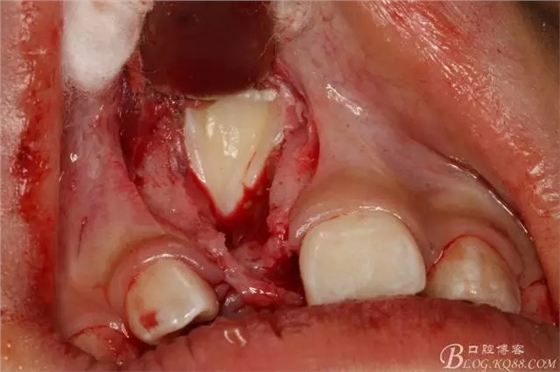

圖8.復位腭側(cè)水平瓣,行唇側(cè)梯形瓣,翻瓣、暴露隆起的骨面。

圖9.去骨、暴露11的舌面